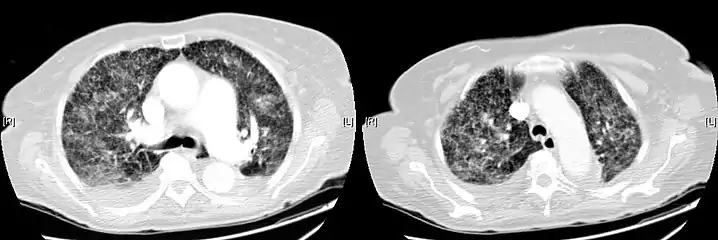

CT, showing extensive pulmonary parenchymal involvement consisting of irregular septal thickenings with ground-glass areas and centrilobular nodules with a peri-lymphatic distribution